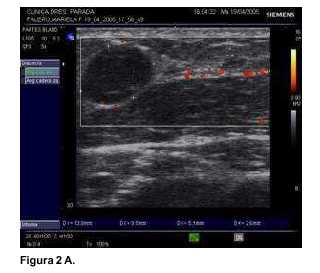

En todas las pacientes la neovascularización se objetivó precozmente mediante la ecografía. En las imágenes obtenidas (figuras 1A, 2A y 3A), se observan como zonas coloreadas en rojo y naranja. Desde el punto de vista endocrino la evolución se presenta en las gráficas contenidas en las figuras (figura 1B: caso 1, figura 2B: caso 2, y figura 3B: caso 3). Se destaca que todas las pacientes presentaban valores normales de E2 y FSH en el preoperatorio.

En el segundo caso (figura 2) se conservan valores de castración aún a los dos meses del posoperatorio. La elevación del E2 con FSH alta también ocurre, pero más tarde, a los cuatro meses, y el reestablecimiento del patrón normal con aparición de folículos madurando ocurre a los ocho meses.

En estos tres casos fue posible sacar conclusiones de los autoinjertos de corteza ovárica a mediano plazo. A diferencia del caso publicado recientemente por nuestro grupo, en el que se mantuvo un ovario intraabdominal translocado(13), en estos casos la evolución depende exclusivamente de los injertos heterotópicos. La ecografía Power Doppler evidencia la enorme capacidad de neo-vascularización que tiene el tejido ovárico. Se trata de un evento precoz, que ya puede observarse dentro de la primera semana. Desde el punto de vista endocrinológico las pacientes, partiendo de una función normal, y luego de operadas, atraviesan un período de "castración" con una FSH muy elevada, 50 mU/ml (paciente 1), 100 mU/ml (paciente 2) y 110 mU/ml (paciente 3), con E2 muy bajo (menor de 10 pg/ml en todas). El primer signo de recuperación es un ascenso del E2 sanguíneo que ocurre al segundo mes en la paciente 1, al cuarto mes en la paciente 2, y al tercer mes en la paciente 3. Finalmente, se produce un descenso de la FSH a valores próximos a la normalidad. La reducción de la FSH está señalando la reestructuración de la granulosa folicular capaz de secretar inhibina, que realiza un "feed back" negativo a nivel hipofisiario con la FSH. En las tres se desarrollaron folículos en maduración, que coincidió con la normalización del estradiol.